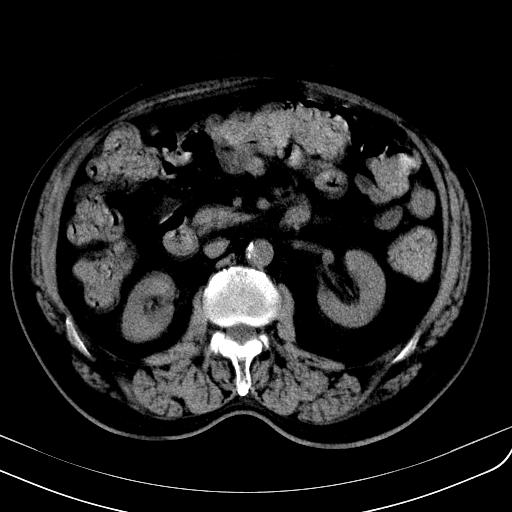

胃底靠近胃大弯处可见一圆形软组织影,直径为3.45cm,ct值约为30.1hu